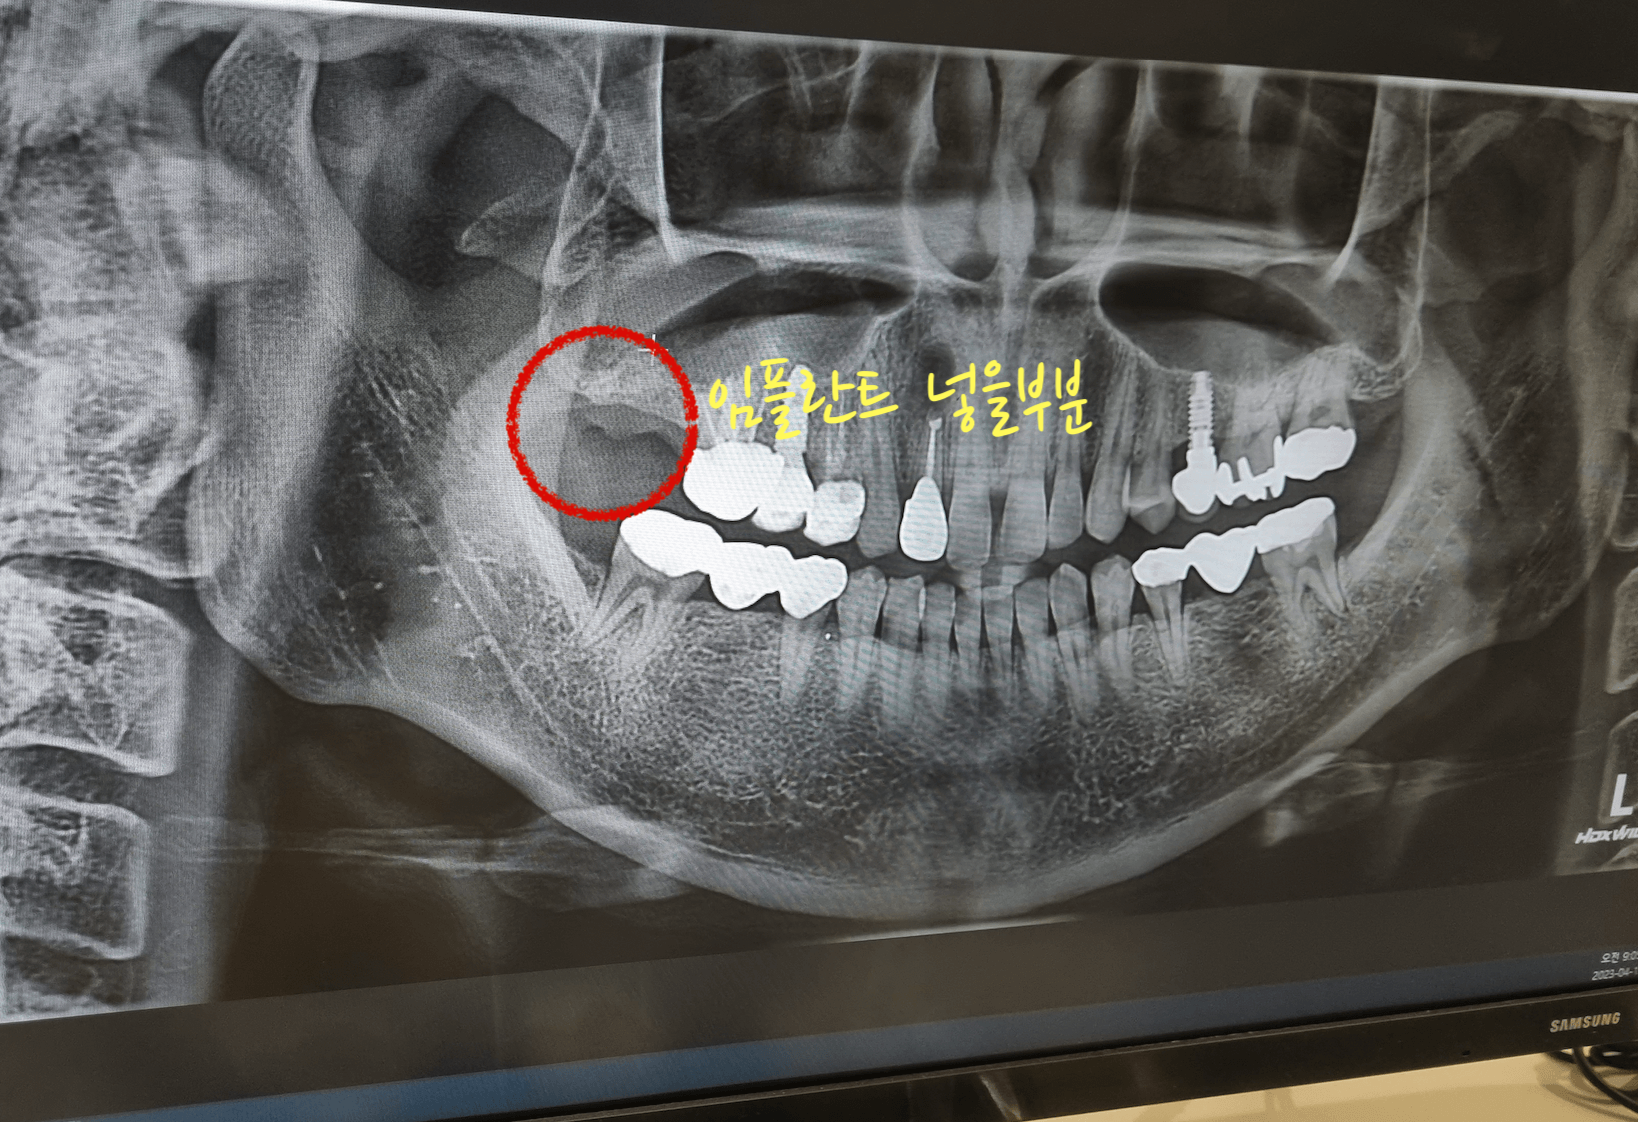

어금니 맨안쪽 치아를 염증 때문에 발치하고 3개월 뒤 어느 정도 뼈가 아물고, 오늘 해당 어금니 부분에 뼈이식과 임플란트 지지대를 삽입하고 왔습니다. 이것까지 하고 나서 치조골 이식한 것과 임플란트가 잘 아물면 그 이후 보철을 씌우면 됩니다.

이번 포스팅의 사진 또한 저의 치아 상태 사진 입니다. 그러니 불법으로 퍼가지 마세요, 부끄럽습니다. 대부분의 치아가 크라운을 씌우거나 임플란트를 해놓은거라 부끄럽네요. 대신 이모든것들이 직접 경험한 내용이기에 팩트는 확실히 전달 될것 같습니다. 아래 포스팅 또한 제가 모두 경험한 내용이니 참고하세요.